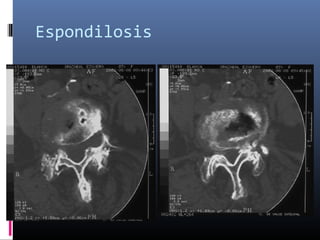

Espondilosis

Fenómeno degenerativo debido a la combinación de los

siguientes factores: Osteofitosis -Nódulo de Schmorl -

Esclerosis de la placa terminal - Degeneración del disco

intervertebral - Hipertrofia de : Lamina, ligamento